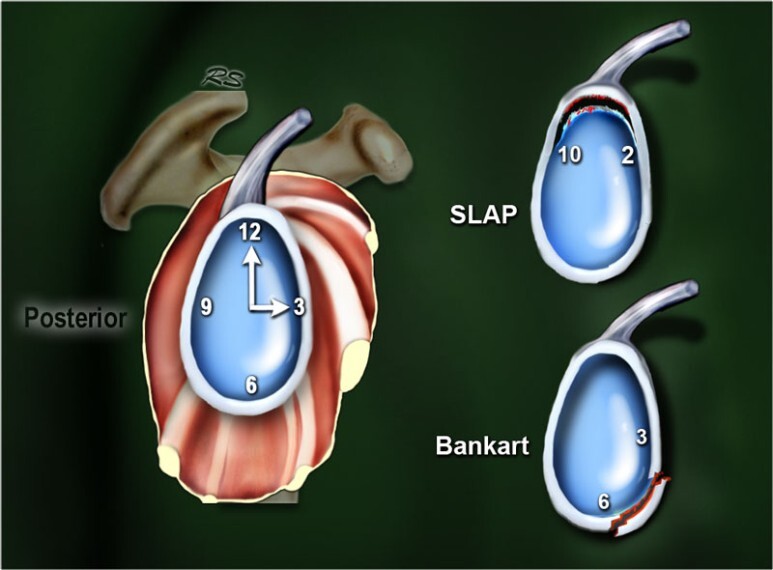

- 어깨 관절 와순(Labrum)은 링처럼 생긴 연골로서 둥그런 어깨 상완골두를 동그랗게 감싸서 안정을 시켜주고, 어깨 손상을 막아주는 중요한 구조물입니다.

- 어느곳에서서 손상이 가능할 수 있지만, 보통 인대가 부착되어 있는 관절와순부위가 당겨지면서 찢어지게 됩니다.

- SLAP 병변은 이 중에서 어깨 관절 와순의 손상입니다. 관절와순에서도 이두근 장두 힘줄이 관절와순과 연결된 부위와 연관되어 발생합니다.